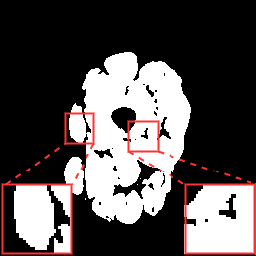

(a) Image

(b) GT

(c) Without

(d) With

To verify the effectiveness of each component in our proposed framework, we conducted a set of ablation studies. Table 1 summarizes the results regarding the data augmentation strategies. Adjusting the contrast of input images reduces the effect from intensity inhomogeneity as evidenced by the improvement on the Dice metrics. Further ablation studies were conducted regarding the PLD stage. When training the model without confidence evaluation (CE), the performance decreases considerably as is supervised by masks that contain potentially incomplete structures. By constraining the supervision signal with CE and (visual examples in Fig. 4), the model is capable of better exploiting the masks.